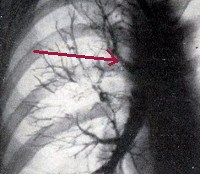

• Бронхологическое обследование. Проводятся фибробронхоскопия и бронхография. Бронхоскопия позволяет обнаружить устье бронхов, плохо расположенных (над Кариной). С помощью бронхографии указывается вариант аномального органа (нештатный или дистопический), определяются его диаметр и длина, оценивается проницаемость, изучается архитектоника трахеобронхиального дерева.

Трахеальный бронх можно заподозрить при рентгенологическом исследовании легких в случае длительной или рецидивирующей локальной инфильтрации в той же области легочной пневмонии. КТ и магнитно-резонансная томография легких выявляют аномальный вариант ветвления трахеи, выявляют патологические изменения в ткани легких, которые связываются с бронхами и бронхоэктазами.